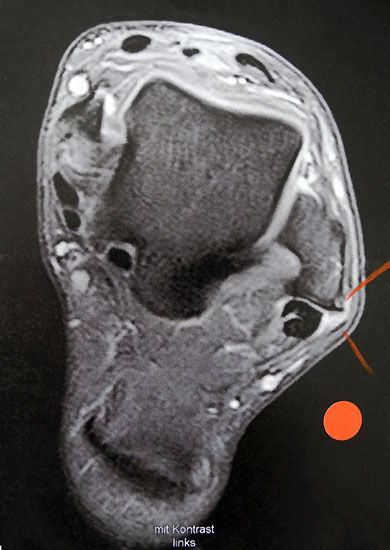

MRT

Unterbrechung des Retinakulums als indirektes Zeichen einer traumatischen Peronealsehnenluxation im MRT.

Abbildung 6

Neben der klinischen Untersuchung besitzt in der Diagnostik von Sehnenpathologie das MRT mit Kontrastmittel einen hohen Stellenwert 8910. Kontrastmittelaufnahme in die Sehne ist immer als Hinweis auf einen Riss zu werten. Weiterhin ist Flüssigkeit im Sehnengleitlager oder die Aufnahme von Kontrastmittel in das Sehnengleitgewebe ein indirektes Zeichen einer Sehnenpathologie.